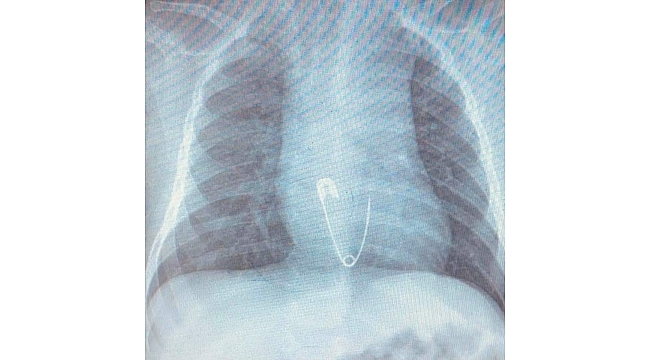

Hastanın Diyarbakır'dan Elazığ'a geldiğini belirten Prof. Dr. Yaşar Doğan, "Hastayı kabul ettik, 5 aylık bir hasta. Bize gelmeden önce üzerinde bulunan nazar boncuğunu çengelli iğne ile birlikte ağzına götürmüş. Aile de fark edince müdahale etmiş, ağzındaki nazar boncuğunu çıkarmış fakat o esnada çengelli iğne yemek borusuna kaçmış. Hasta geldiği zaman çektiğimiz röntgende çengelli iğne yemek borusunun alt kısmında takılı vaziyetteydi. Hastaya 15 dakikalık sedasyon altında işlem yapıldı, endoskopi ile parça çıkarıldı. Hasta şu anda gayet iyi. Biraz sonra da evlerine göndereceğiz" dedi.